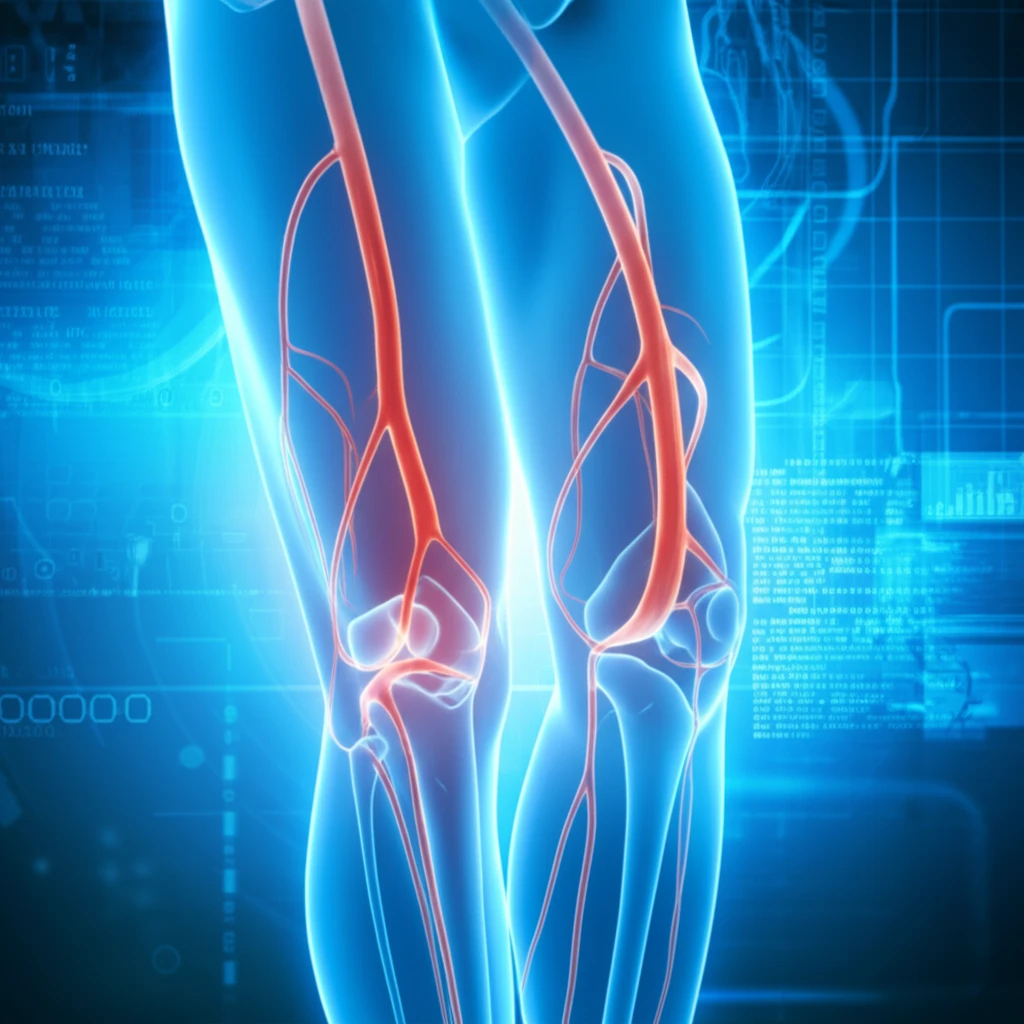

Peripheral Artery Disease (PAD), a condition marked by the narrowing of arteries, often goes unnoticed until it progresses, potentially leading to severe complications like limb amputation. Traditional diagnostic methods often involve invasive procedures or the use of contrast agents, which carry risks. However, recent advancements in medical imaging are offering new hope. Non-contrast MR angiography is emerging as a powerful, non-invasive tool, promising a safer and more effective way to detect and characterize PAD.

This article delves into a groundbreaking study that compares the diagnostic accuracy of non-contrast MR angiography protocols with the conventional, contrast-enhanced method. The research focuses on two primary non-contrast techniques performed at 3T (a type of MRI machine), assessing their ability to evaluate lower extremity PAD. The goal is to determine if these innovative methods can match the effectiveness of traditional approaches while minimizing patient risk.

Non-contrast MR angiography utilizes advanced imaging techniques that do not require the use of gadolinium-based contrast agents. This is a significant advantage, as contrast agents can pose risks, including allergic reactions and nephrogenic systemic fibrosis, particularly for patients with kidney problems. The core of these techniques lies in capturing detailed images of blood vessels without the need for these agents.